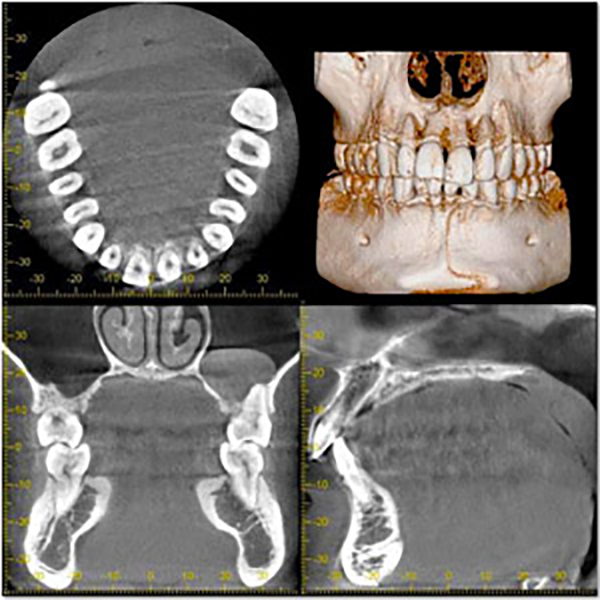

院内にCT装置を設置しています。

インプラント治療や親知らずの抜歯、根管治療など、精密な治療を行うため、様々な治療で利用します。